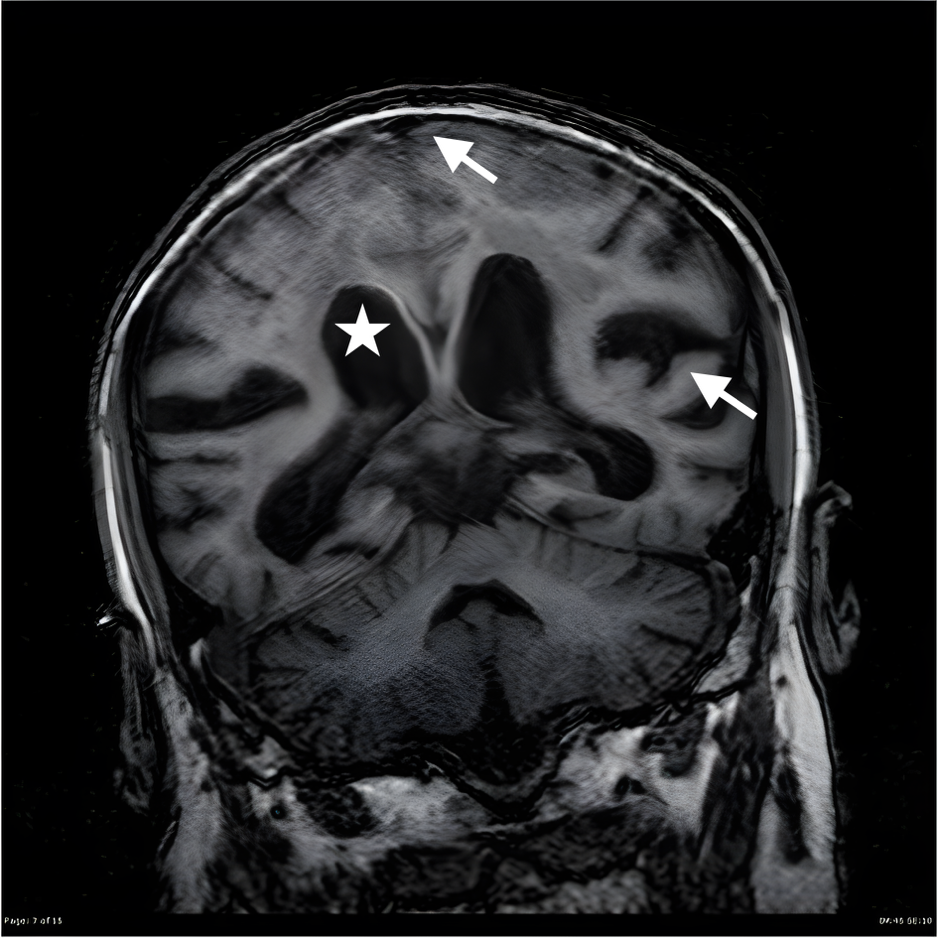

Hình 3. Dấu hiệu DESH trên MRI sọ não đặc trưng cho biểu hiện giãn não thất áp lực bình thường với giãn não thất (ngôi sao), rãnh vỏ não vùng đỉnh bị xẹp, rãnh Sylvius giãn (dấu mũi tên)

Dấu hiệu đặc trưng trên MRI:

- Giãn sừng trán não thất bên.

- Giảm khoảng cách rãnh cuộn não vùng đỉnh – đỉnh chẩm.

- Dấu hiệu DESH (Disproportionately Enlarged Subarachnoid Space Hydrocephalus) – một đặc điểm gợi ý mạnh cho NPH.